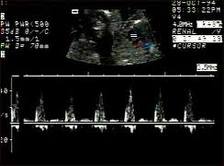

Hola, mi última menstruación fue el 14 de octubre de 2022. El 15 de diciembre me dicen que tengo un embrón de 2mm sin latido. Por lo visto no corresponden las semanas al tamaño. Vuelvo el 20 de diciembre y tanto el saco como el embrión han crecido, ahora el embrión es de 4mm. Me han dicho que vuelva el 26 de diciembre y si sigue sin latido me harán abortar. ¿Creeis que puedo tener esperanzas?